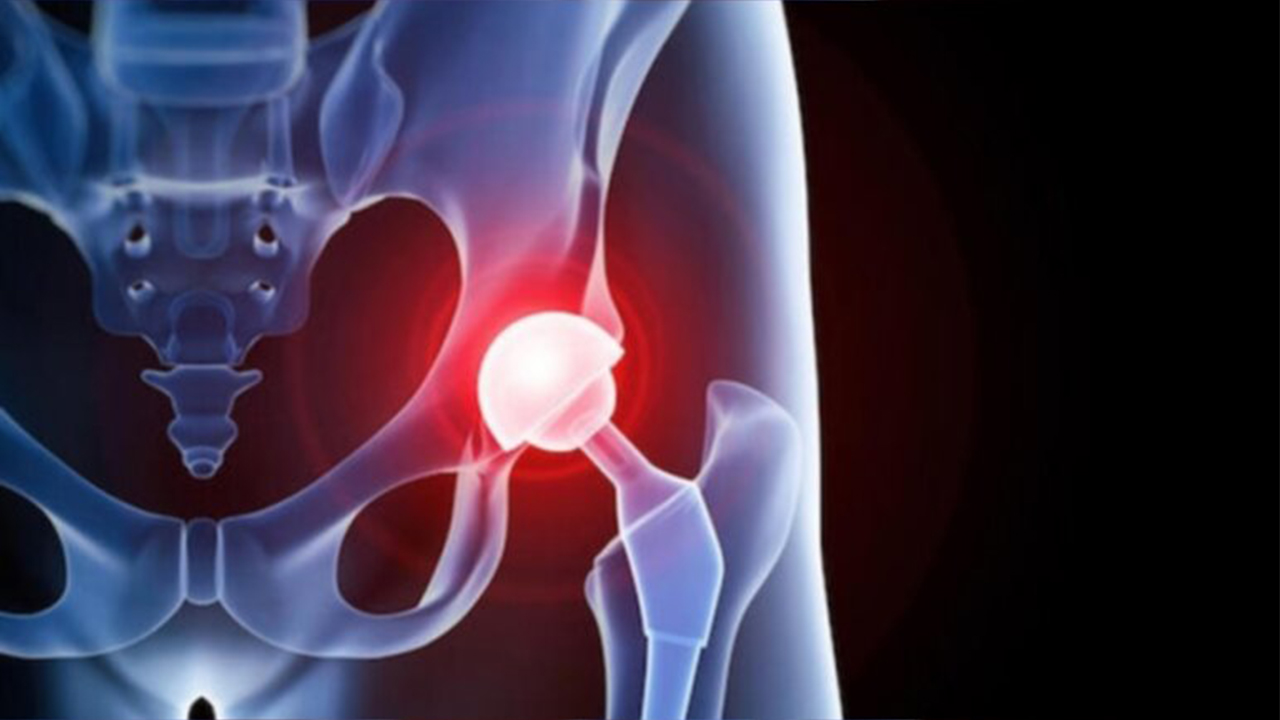

Замена таз сустава

Замена таз сустава 113 фотографий